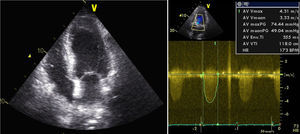

O ecocardiograma transtorácico (Figura 1) mostrou ventrículo esquerdo não dilatado, com ligeira hipertrofia do septo interventricular, com boa função sistólica global (FSG) e segmentar; válvula aórtica fibrocalcificada com gradiente transvalvular máximo de 74 e médio de 49mmHg e área calculada por equação de continuidade de 0,77cm2.